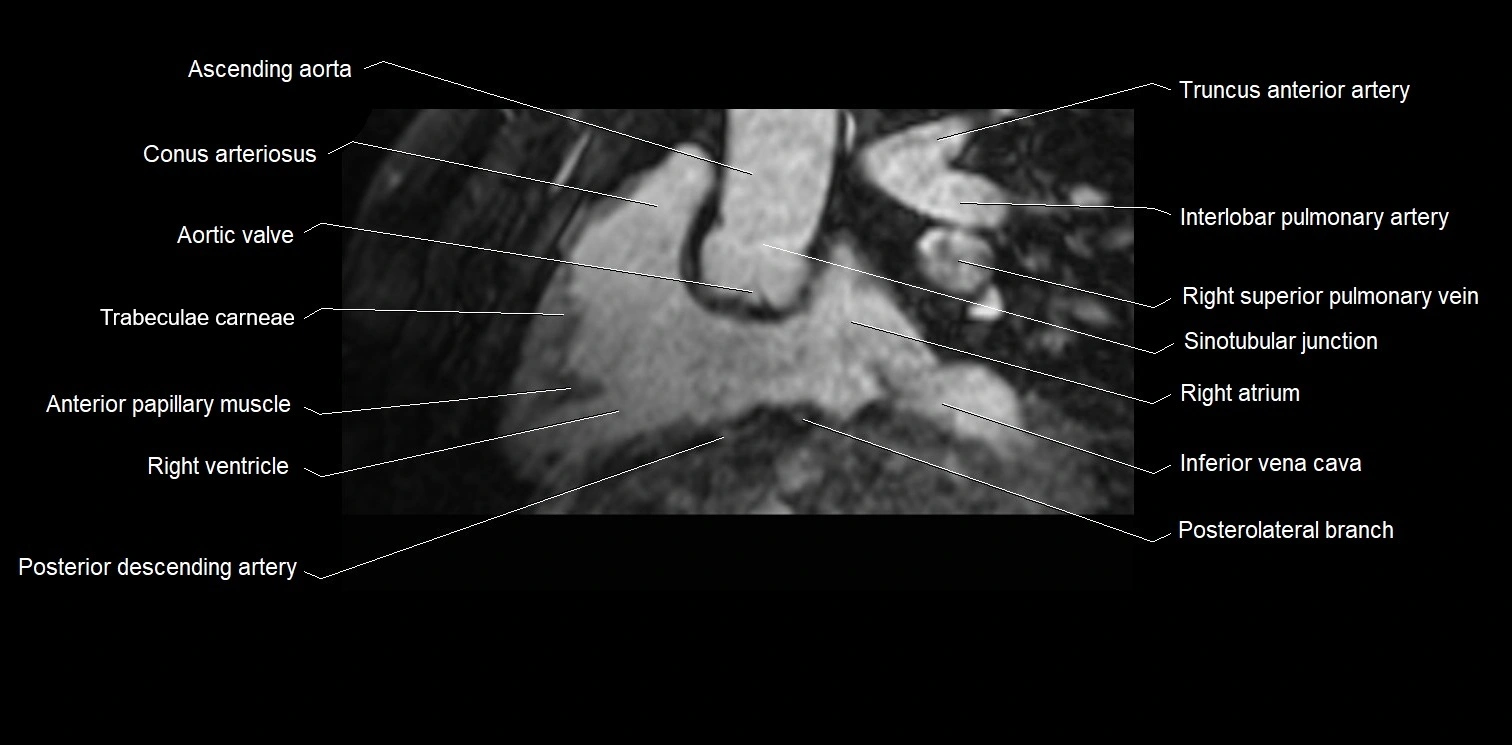

MRI image